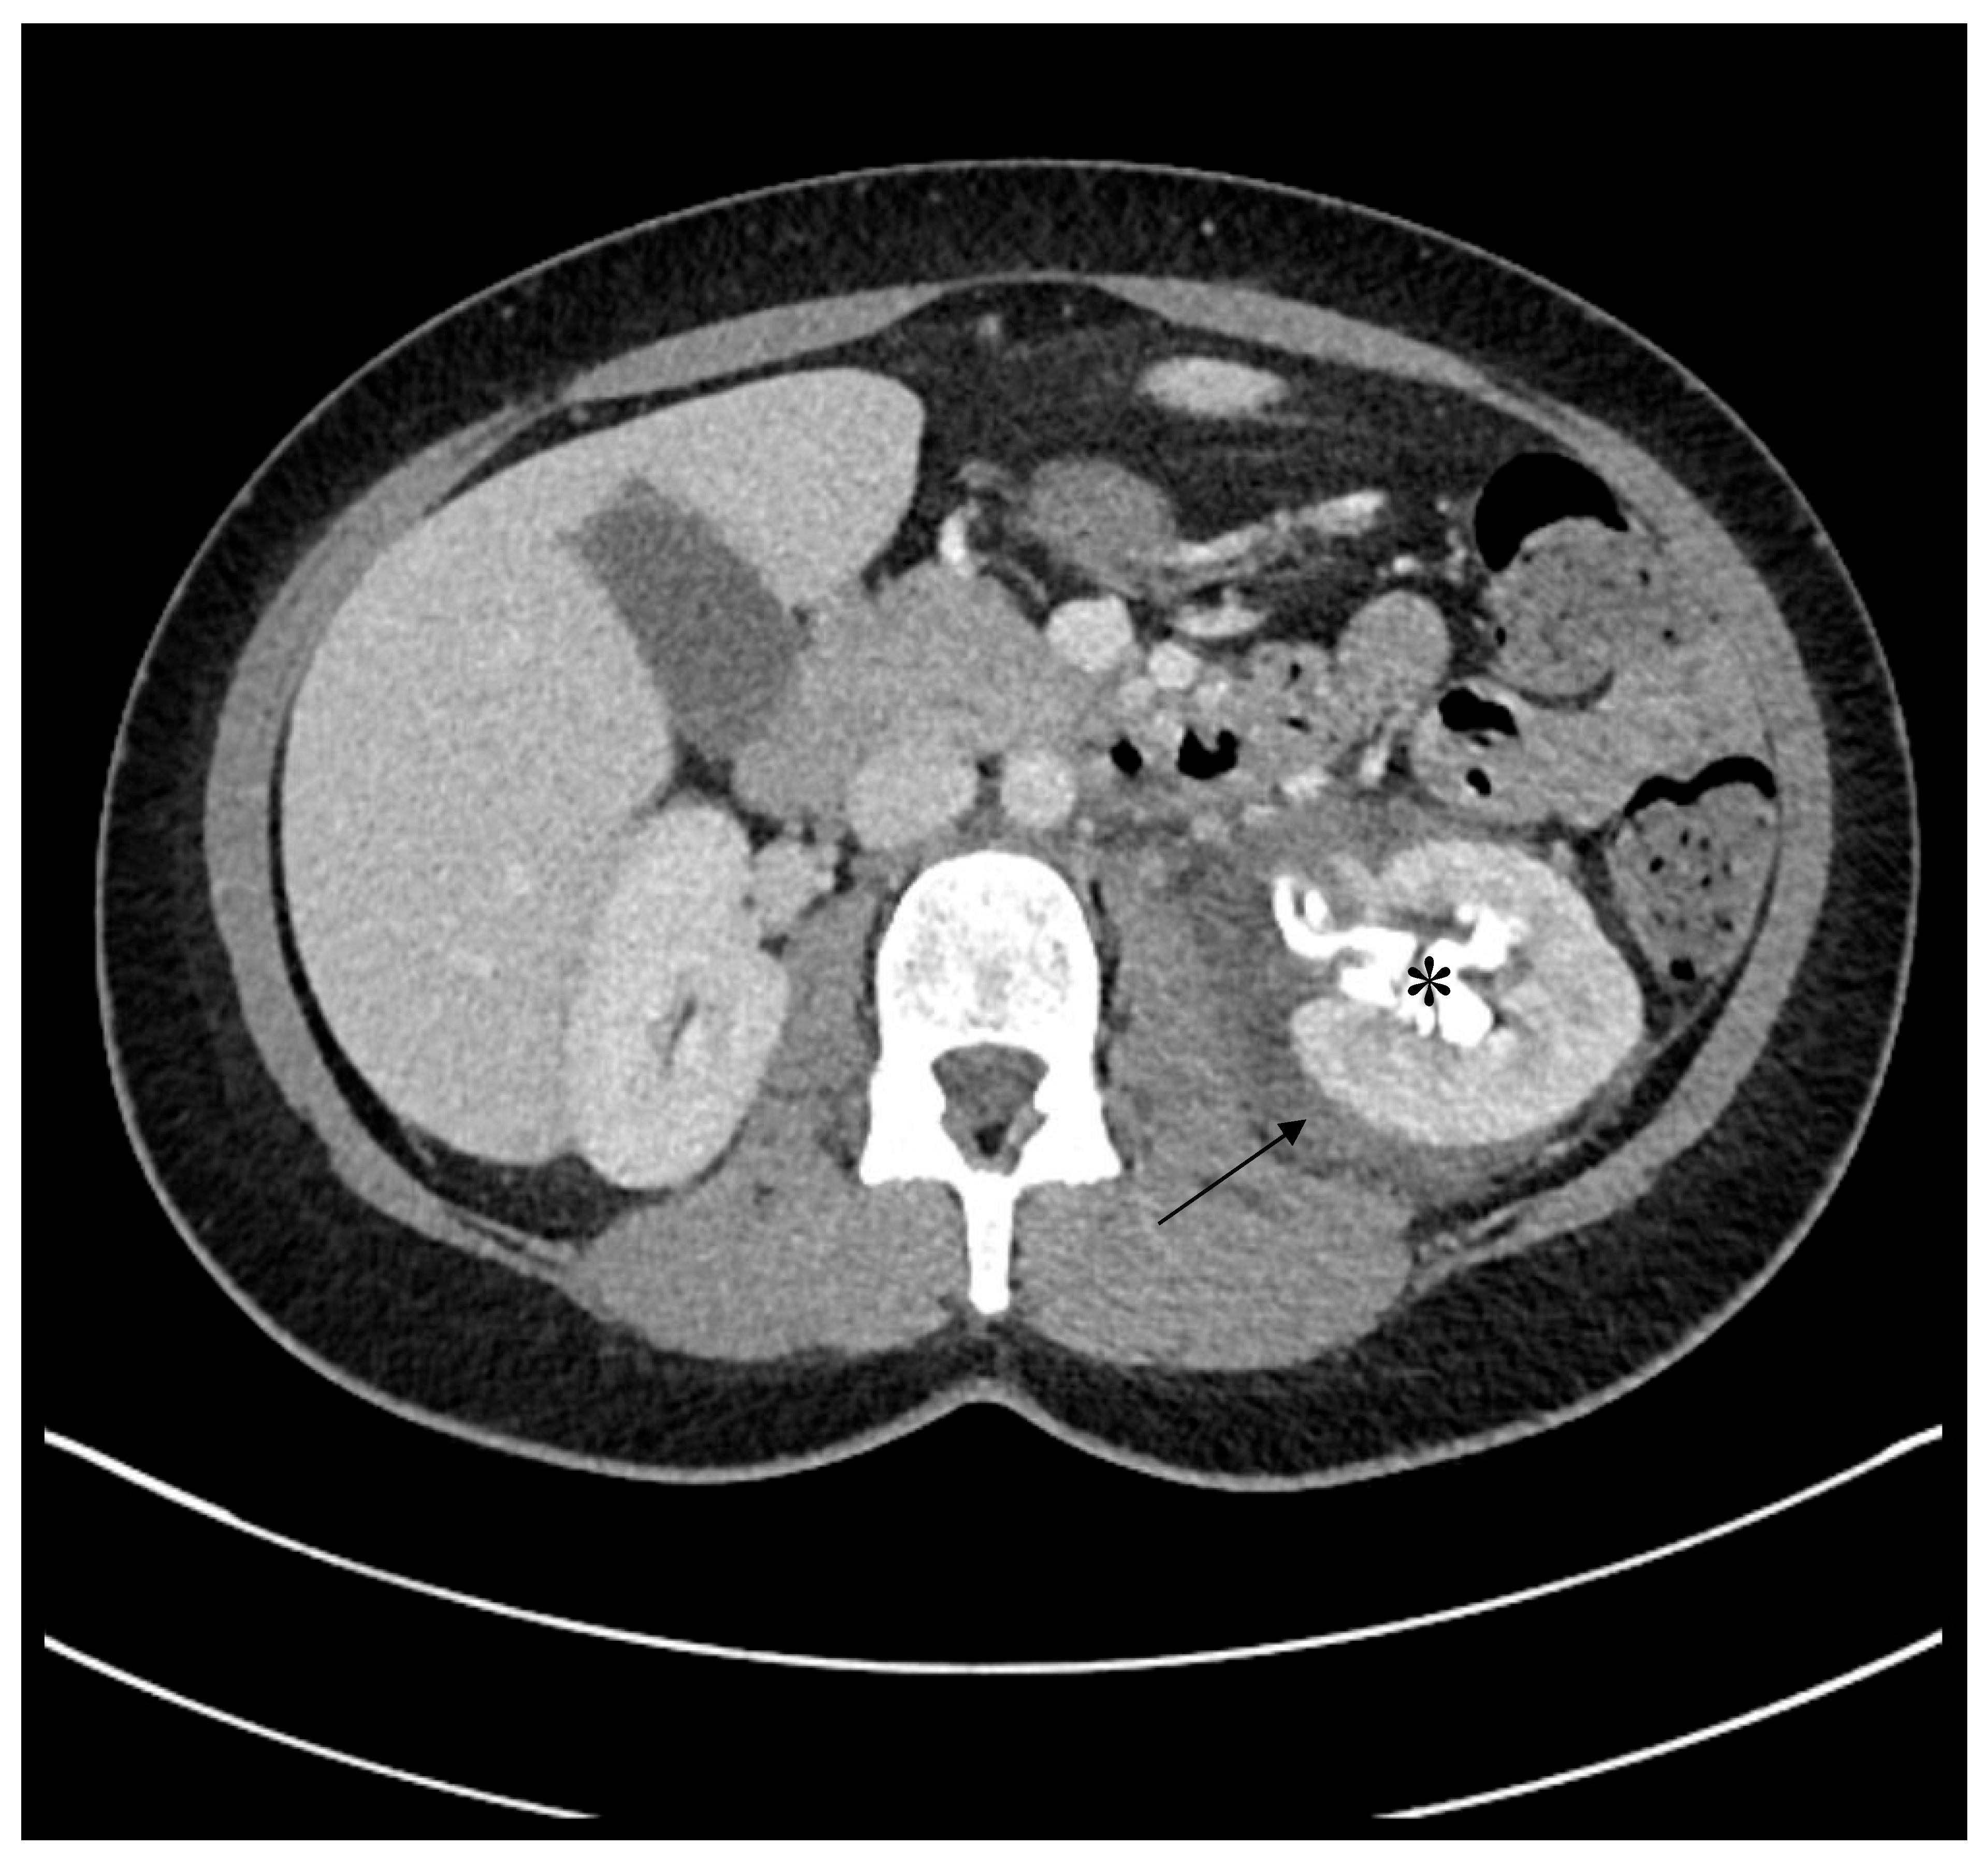

2. Case